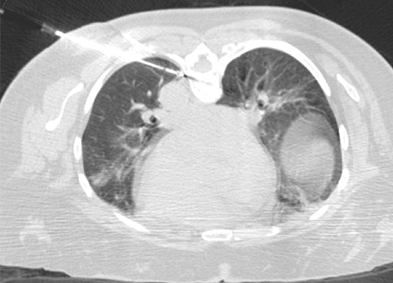

Crioablación de mCRC en el pulmón ubicado junto a la aorta

Una mujer de 57 años con antecedentes de metástasis pulmonares de cáncer colorrectal presentó una nueva metástasis pulmonar de 1 cm identificada en el lóbulo inferior izquierdo. Se realizó la crioablación con una aguja IceSphere™ 1.5 y se inyectó CO2 en el espacio pleural para mover la metástasis lejos de la aorta y prevenir posibles daños a la aorta, así como evitar el efecto de disipación de calor que reduciría las posibilidades de ablación completa. La característica única de "modo de adherencia" ofrecida por la crioablación permite mover el tumor lejos de órganos adyacentes vulnerables, y en consecuencia, tratar tumores pulmonares técnicamente desafiantes de manera segura y efectiva.

Thierry de Baere, MD I Instituto de Cáncer Gustave Roussy I Villejuif, Francia